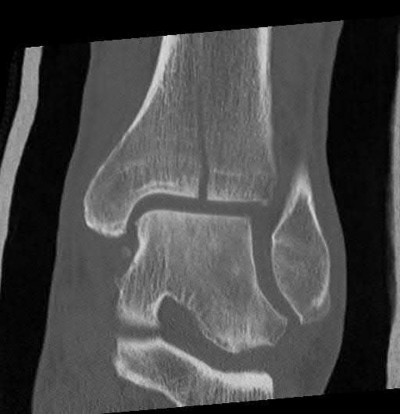

A 25-year-old female is involved in a motor vehicle collision. She presents with the isolated injury seen in Figures A through D. Her leg is swollen but her skin is intact. She has no clinical signs of compartment syndrome. Which of the following treatment options will allow for maintenance of fracture alignment and minimize the risk of soft tissue complications?

The patient presents with a closed distal third metaphyseal-diaphyseal distal tibia fracture with simple intra-articular extension. Immediate intramedullary nailing along with percutaneous fixation of the articular component provides appropriate restoration of length, rotation and alignment and minimizes the risk of wound complication.

Displaced distal third tibia fractures may be associated with simple intraarticular extension. Operative treatment of intra-articular distal tibia fractures has historically been performed with open reduction and internal fixation. Early open reduction and plate fixation of pilon fractures has been associated with high rates of infection and wound complication. In select patterns with simple articular extension, percutaneous screw fixation and medullary nailing may provide appropriate reduction with minimal soft-tissue risk.

Figures A and B demonstrate a distal third tibial shaft fracture with simple intra-articular extension. The axial and coronal CT cuts in Figures C and D further clarify the articular injury. Illustrations A and B demonstrate a comminuted distal third tibial fracture with simple intra-articular extension. Illustrations C and D are fluoroscopic images of the same injury after intramedullary nailing and percutaneous fixation of the articular component.